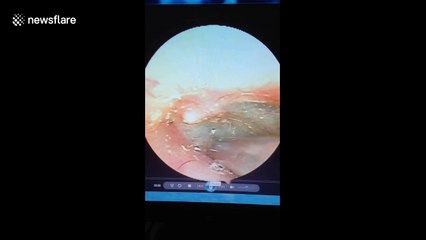

Chinese doctor removes spider that was weaving webs in woman's ear

A doctor in south China removed a live spider weaving webs in a woman's ear on April 22.br br The video, filmed in the city of Mianyang in Sichuan Province, shows a three-millimetre spider crawling around in a woman's ear weaving webs.br br According to reports, the woman's ear was itchy and had tinnitus after she did some work in the yard.br br The doctor named Liu Jun put some liquid medicine into the woman's ear to sedate the spider before taking it out.br br Fortunately, as the spider is small, the woman's hearing was not damaged.br br The video was provided by local media with permission.